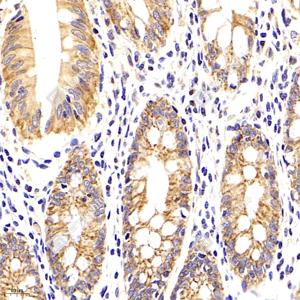

IHC检测Claudin 5蛋白(货号 GB11290). 样品: 人结肠癌, 4%多聚甲醛 (货号G1101) 固定12-24小时. 抗原修复: 柠檬酸抗原修复液(干粉, pH 6.0) (G1201), 98℃, 20分钟. —抗: 1: 700稀释, 4℃ 孵育过夜. 二抗: HRP标记山羊抗兔IgG (H+L) (货号GB23303), 1: 200稀释, 室温孵育1小时. |

IHC检测Claudin 5蛋白(货号 GB11290). 样品: 人结肠, 4%多聚甲醛 (货号G1101) 固定12-24小时. 抗原修复: 柠檬酸抗原修复液(干粉, pH 6.0) (G1201), 98℃, 20分钟. —抗: 1: 700稀释, 4℃ 孵育过夜. 二抗: HRP标记山羊抗兔IgG (H+L) (货号GB23303), 1: 200稀释, 室温孵育1小时. |